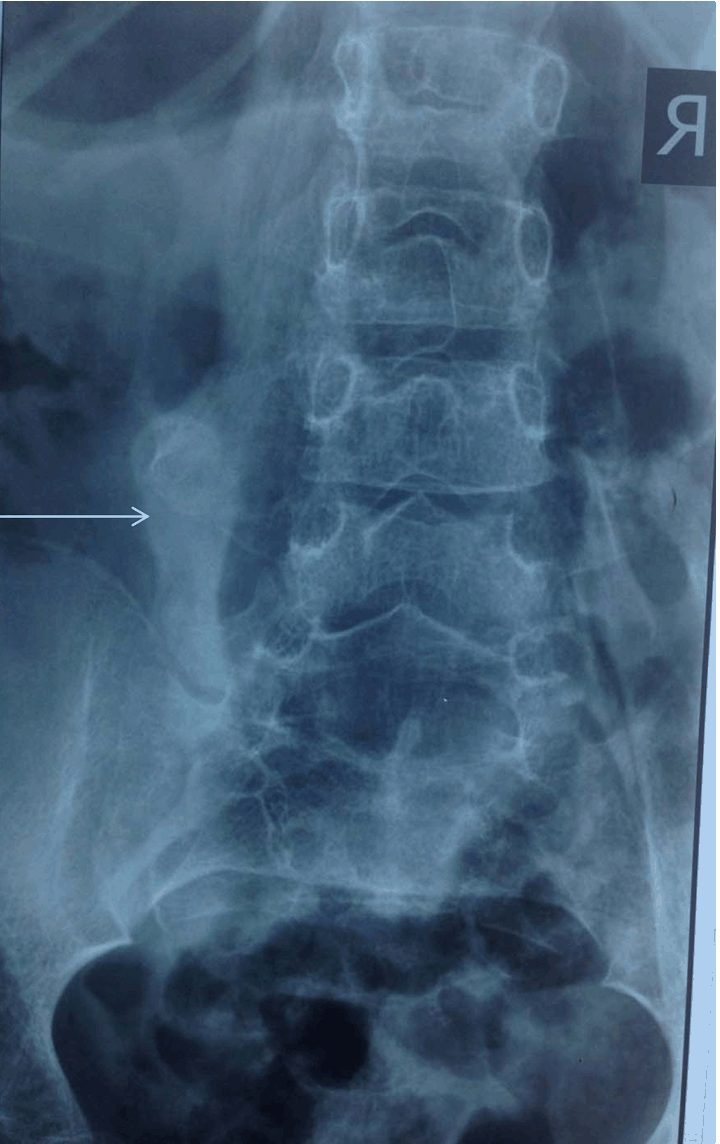

X-ray of cervical spine showed calcific strands around both shoulder joints (left more than right) and in the paraspinal regions. (Figure 4) A detailed skeletal survey of the body revealed calcification in the soft tissues surrounding the cervical region, left shoulder, in the anterior chest wall, the thorax, and the paraspinal muscles and knee. (Figure 5) Considering both the clinical and the radiological features, sporadic myositis ossificans progressiva was diagnosed. The child was treated with graded physiotherapy. Bisphosphonates were added. As there was no acute flare-up, steroids were not given. The patient has been followed-up for one year. No new lumps have been noticed after starting of bisphosphonates.

Figure 5: Calcifications around paraspinal muscles (arrow).